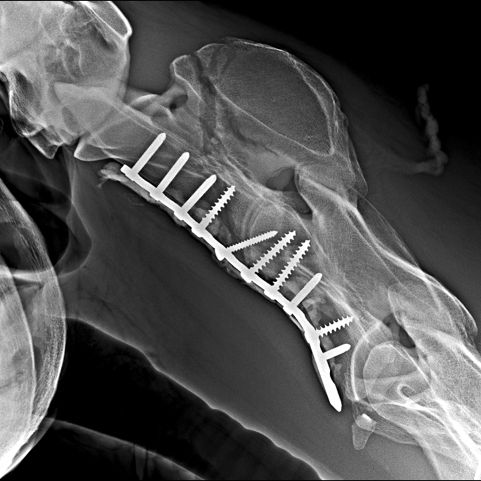

Die GPM ist stolz Dr. Fabrice Rossignol für die Networking Days 2026 (Tickets gibt's HIER!) als Referent ankündigen zu können. Mit seinen beiden Vorträgen "Cervical spine surgery – What is possible?" und "Upper airway surgery – Where are we headed?" berichtet er aus seinen beiden Spezialgebieten und bietet zum Thema Chirurgie an der Halswirbelsäule zudem mit Prof. Dr. Christoph Lischer (DipECVS, Pferdeklinik FU Berlin) noch einen ganztägigen Workshop an (In-depth session on cervical spine surgery incl. Wetlab demonstration).

Fabrice ist leitender Chirurg an der Pferdeklinik Grosbois sowie an der Klinik von Chantilly. Er ist zu 100 % chirurgisch tätig und hat ein besonderes Interesse an der Chirurgie der oberen Atemwege, der Frakturversorgung sowie der Wirbelsäulenchirurgie.

Er ist an mehreren Forschungsprojekten zur Physiologie und Biomechanik des Kehlkopfs sowie zur Kehlkopf-Reinnervation beteiligt. Seit 2016 ist er zudem Mitglied und Vorsitzender der AOVET Large Animal Expert Group und Faculty und engagiert sich aktiv in der Entwicklung neuer orthopädischer Implantate.